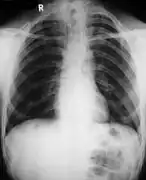

Cleidocranial dysostosis (CCD), also called cleidocranial dysplasia, is a birth defect that mostly affects the bones and teeth.[1] The collarbones are typically either poorly developed or absent, which allows the shoulders to be brought close together.[1] The front of the skull often does not close until later, and those affected are often shorter than average.[1] Other symptoms may include a prominent forehead, wide set eyes, abnormal teeth, and a flat nose.[1] Symptoms vary among people; however, intelligence is typically unaffected.[1]

Cleidocranial dysostosis is a general skeletal condition[8] so named from the collarbone (cleido-) and cranium deformities which people with it often have.

• Clavicles (collarbones) can be partly missing leaving only the medial part of the bone. In 10% of cases, they are completely missing.[10] If the collarbones are completely missing or reduced to small vestiges, this allows hypermobility of the shoulders including ability to touch the shoulders together in front of the chest.[11] The defect is bilateral 80% of the time.[12] Partial collarbones may cause nerve damage symptoms and therefore have to be removed by surgery.

Different features of the dysostosis are significant. Radiological imaging helps confirm the diagnosis. During gestation (pregnancy), clavicular size can be calculated using available nomograms. Wormian bones can sometimes be observed in the skull.[20]